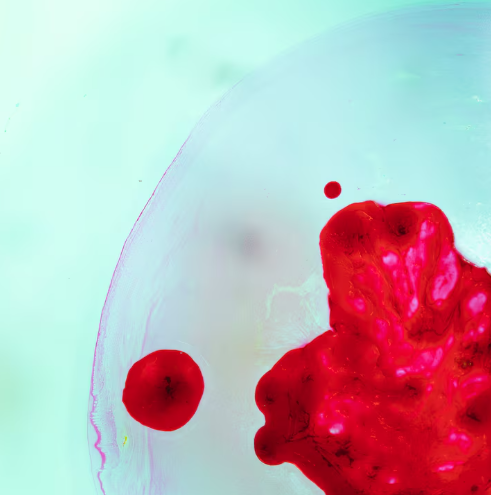

La hemofilia es un trastorno hemorrágico hereditario poco frecuente que afecta la capacidad de coagulación de la sangre y puede provocar sangrados prolongados o espontáneos, incluso ante lesiones menores. Aunque no tiene cura, con diagnóstico y tratamiento adecuados es posible llevar una vida plena y activa. No obstante, a nivel global, la detección temprana de esta condición continúa siendo uno de los principales desafíos para garantizar una atención integral y oportuna.

Trastornos de coagulación